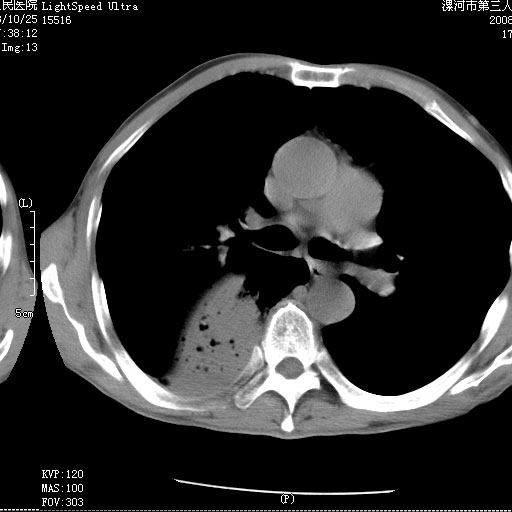

m 老年 发烧、呼吸困难,慢支、肺气肿多年;记的那次是下午大概17:38做的,晚上窒息死亡。

上面的层面就慢性支气管炎肺气肿、肺大泡,别的没有什么、也就不传了。

当时我怀疑:1、阻塞性肺不张早期 2、肺脓肿早期,望老师们发表意见

1、右侧脓胸;2、copd;

3、细支气管肺泡癌可以排除,病变以斜裂为界,呈大片状高密度影,内可见多发小气泡,表明有产气杆菌感染所致,内无明显的支气管“枯树枝征”表现,再结合其临床改变(细支气管肺泡癌临表表现重、影像表现轻)所以不符合细支气管肺泡癌(炎症型)的改变。

按肺叶分布,考虑肺不张

病变按肺叶分布,病变内可见多个小空腔影,未见充气支气管影,中间段支气管管腔肺窗示密度欠均匀,下肺支气管分叉处基底段支气管隐约可见,未见明显狭窄,中叶支气管通畅,

考虑:阻塞性肺炎伴小脓肿形成可能性大。(痰栓可能性大)

叶间裂前移,能考虑肺不张和肺栓塞吗?为什么不增强?大叶肺炎不能考虑吗?

右下肺实变,内有弥漫分面小气泡而无支气管征,叶间裂前移,呈臌大之形,而无收缩之状,兼纵隔稍左行移,故。不支持不张,倒支持大叶肺叶,如楼上所说,小气泡不象残留之肺,不可以考虑产气菌感染吗。

阻塞性肺炎,肺脓肿形成。依据,右下支气管不通,大片实变形内可见小气泡。不支持肺不张。

坠积性肺炎合并右下肺膨胀不全

右下肺阻塞性炎症,内见多发气体影,以肺叶分布.不支持不张.

右肺下叶肺脓肿,右肺下叶支气管痰栓形成。

考虑右肺下叶脓肿,右肺下叶支气管痰栓。